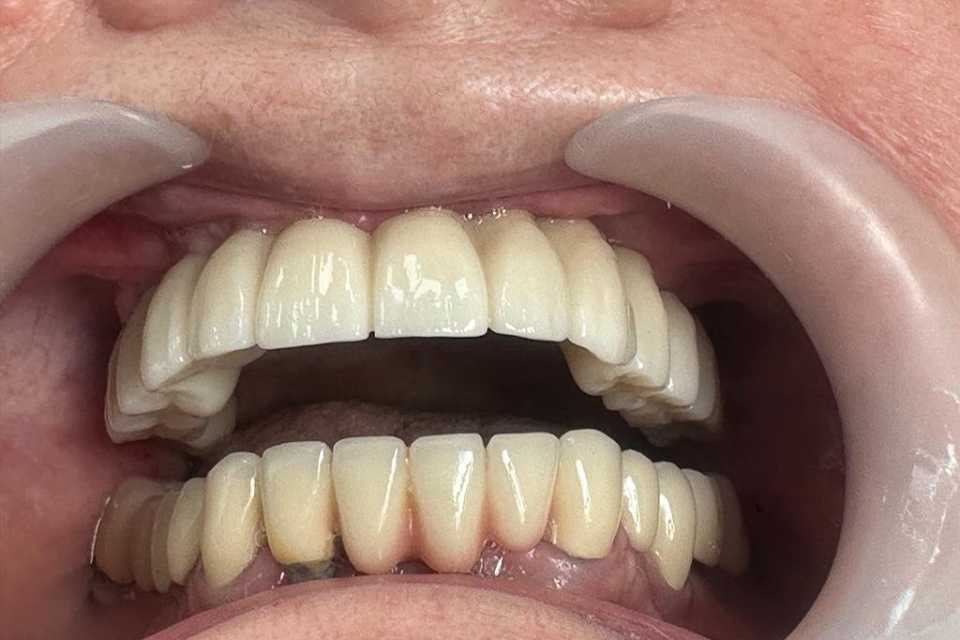

Pacienta, în vârstă de 75 de ani, a fost purtătoare de proteză dentară mobilă timp de peste 15 ani. În urmă cu 2 ani, a încercat o procedură chirurgicală de inserare a implanturilor orale standard și adiție osoasă, însă intervenția nu a avut succes.

Se prezintă acum în clinica noastră cu dorința de a obține o dantură fixă.

Pentru a răspunde nevoilor sale, s-a optat pentru utilizarea unor implanturi orale speciale: 4 implanturi zigomatice, 2 implanturi pterigoide și 1 implant standard. Această abordare a permis reabilitarea completă a arcadei dentare superioare printr-o lucrare protetică fixă, înșurubabilă, realizată din ceramică pe suport de zirconiu.